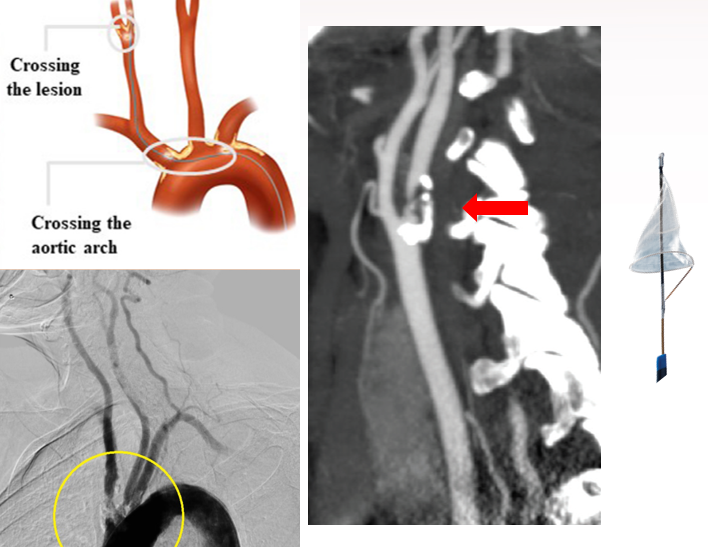

栓塞事件的风险高:在建立通路过程中,左颈总动脉或无名动脉开口处以及颈动脉的狭窄病变可能发生斑块破裂、栓子脱落等引起远端栓塞。

通路建立困难或稳定性不足:在血管形态不良及血管病变,如部分Ⅱ型主动脉弓、Ⅲ型主动脉弓及牛角弓以及起源于主动脉弓上的血管包括无名动脉、左颈总动脉主干狭窄或血管形态迂曲,这些血管变化可导致通路建立困难或稳定性不足。

2015年,经颈动脉血运重建术(Trans-Carotid Artery Revascularization, TCAR)使上述不足得到解决,其经颈动脉直接入路并通过逆向血流装置,降低顺行栓塞风险。具有创伤小,切口远离颅神经,术中无需使用脑保护装置等优点。

是我们自主最新研发的一套血运重建系统,由3个核心部分组成:

PT-CAS经颈动脉腔内血运重建系统

PT-CAS颈动脉支架

PT-CAS血管闭合装置

建立逆向血流保护机制

避免逆向血流盲端

避免刺激颈动脉斑块

将来有可能避免切口、完全经皮进行

PT-CAS与TCAR的比较:

与TCAR相比,PT-CAS的明显优势在于:没有逆向血流盲端、避免刺激斑块、完全经皮操作。